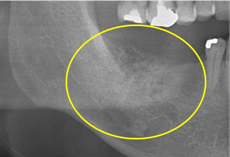

抜歯のう胞摘出

Perio Wave+Er:YAGレーザー+コールドレーザーで治療した箇所の経過です。

左から直後、1ヶ月経過時、2ヶ月経過時の画像です。

骨再生の確認をした際の動画です。

画像をクリックすると、youtubeにジャンプします。

骨再生

骨再生した箇所にインプラントを埋入します。

CTで治療計画を綿密に練ったうえで行いました。

インプラント埋入の際の動画です。

インプラント埋入

インプラント埋入後のレントゲン画像です。